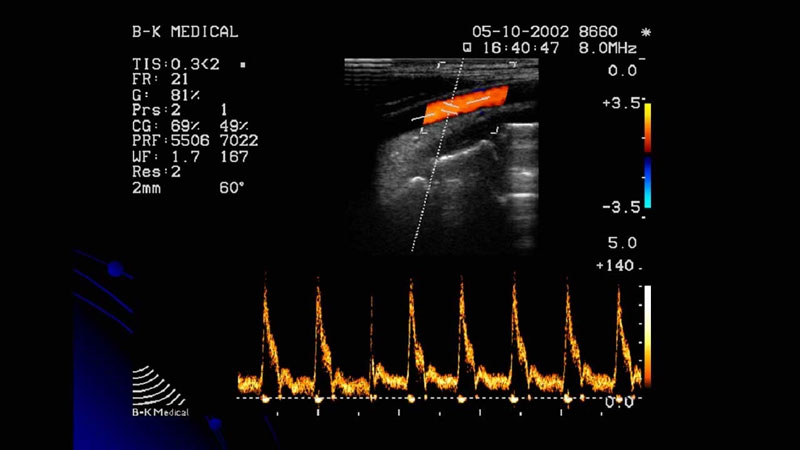

Siêu âm Doppler màu: Đây là một dạng siêu âm Doppler tim nâng cao để đo và đánh giá lưu lượng máu, buồng bơm và van tim. Đồng thời, phát hiện lưu lượng máu bất thường trong tim.

Siêu âm Doppler là kỹ thuật quan trọng trong chẩn đoán các vấn đề về tim